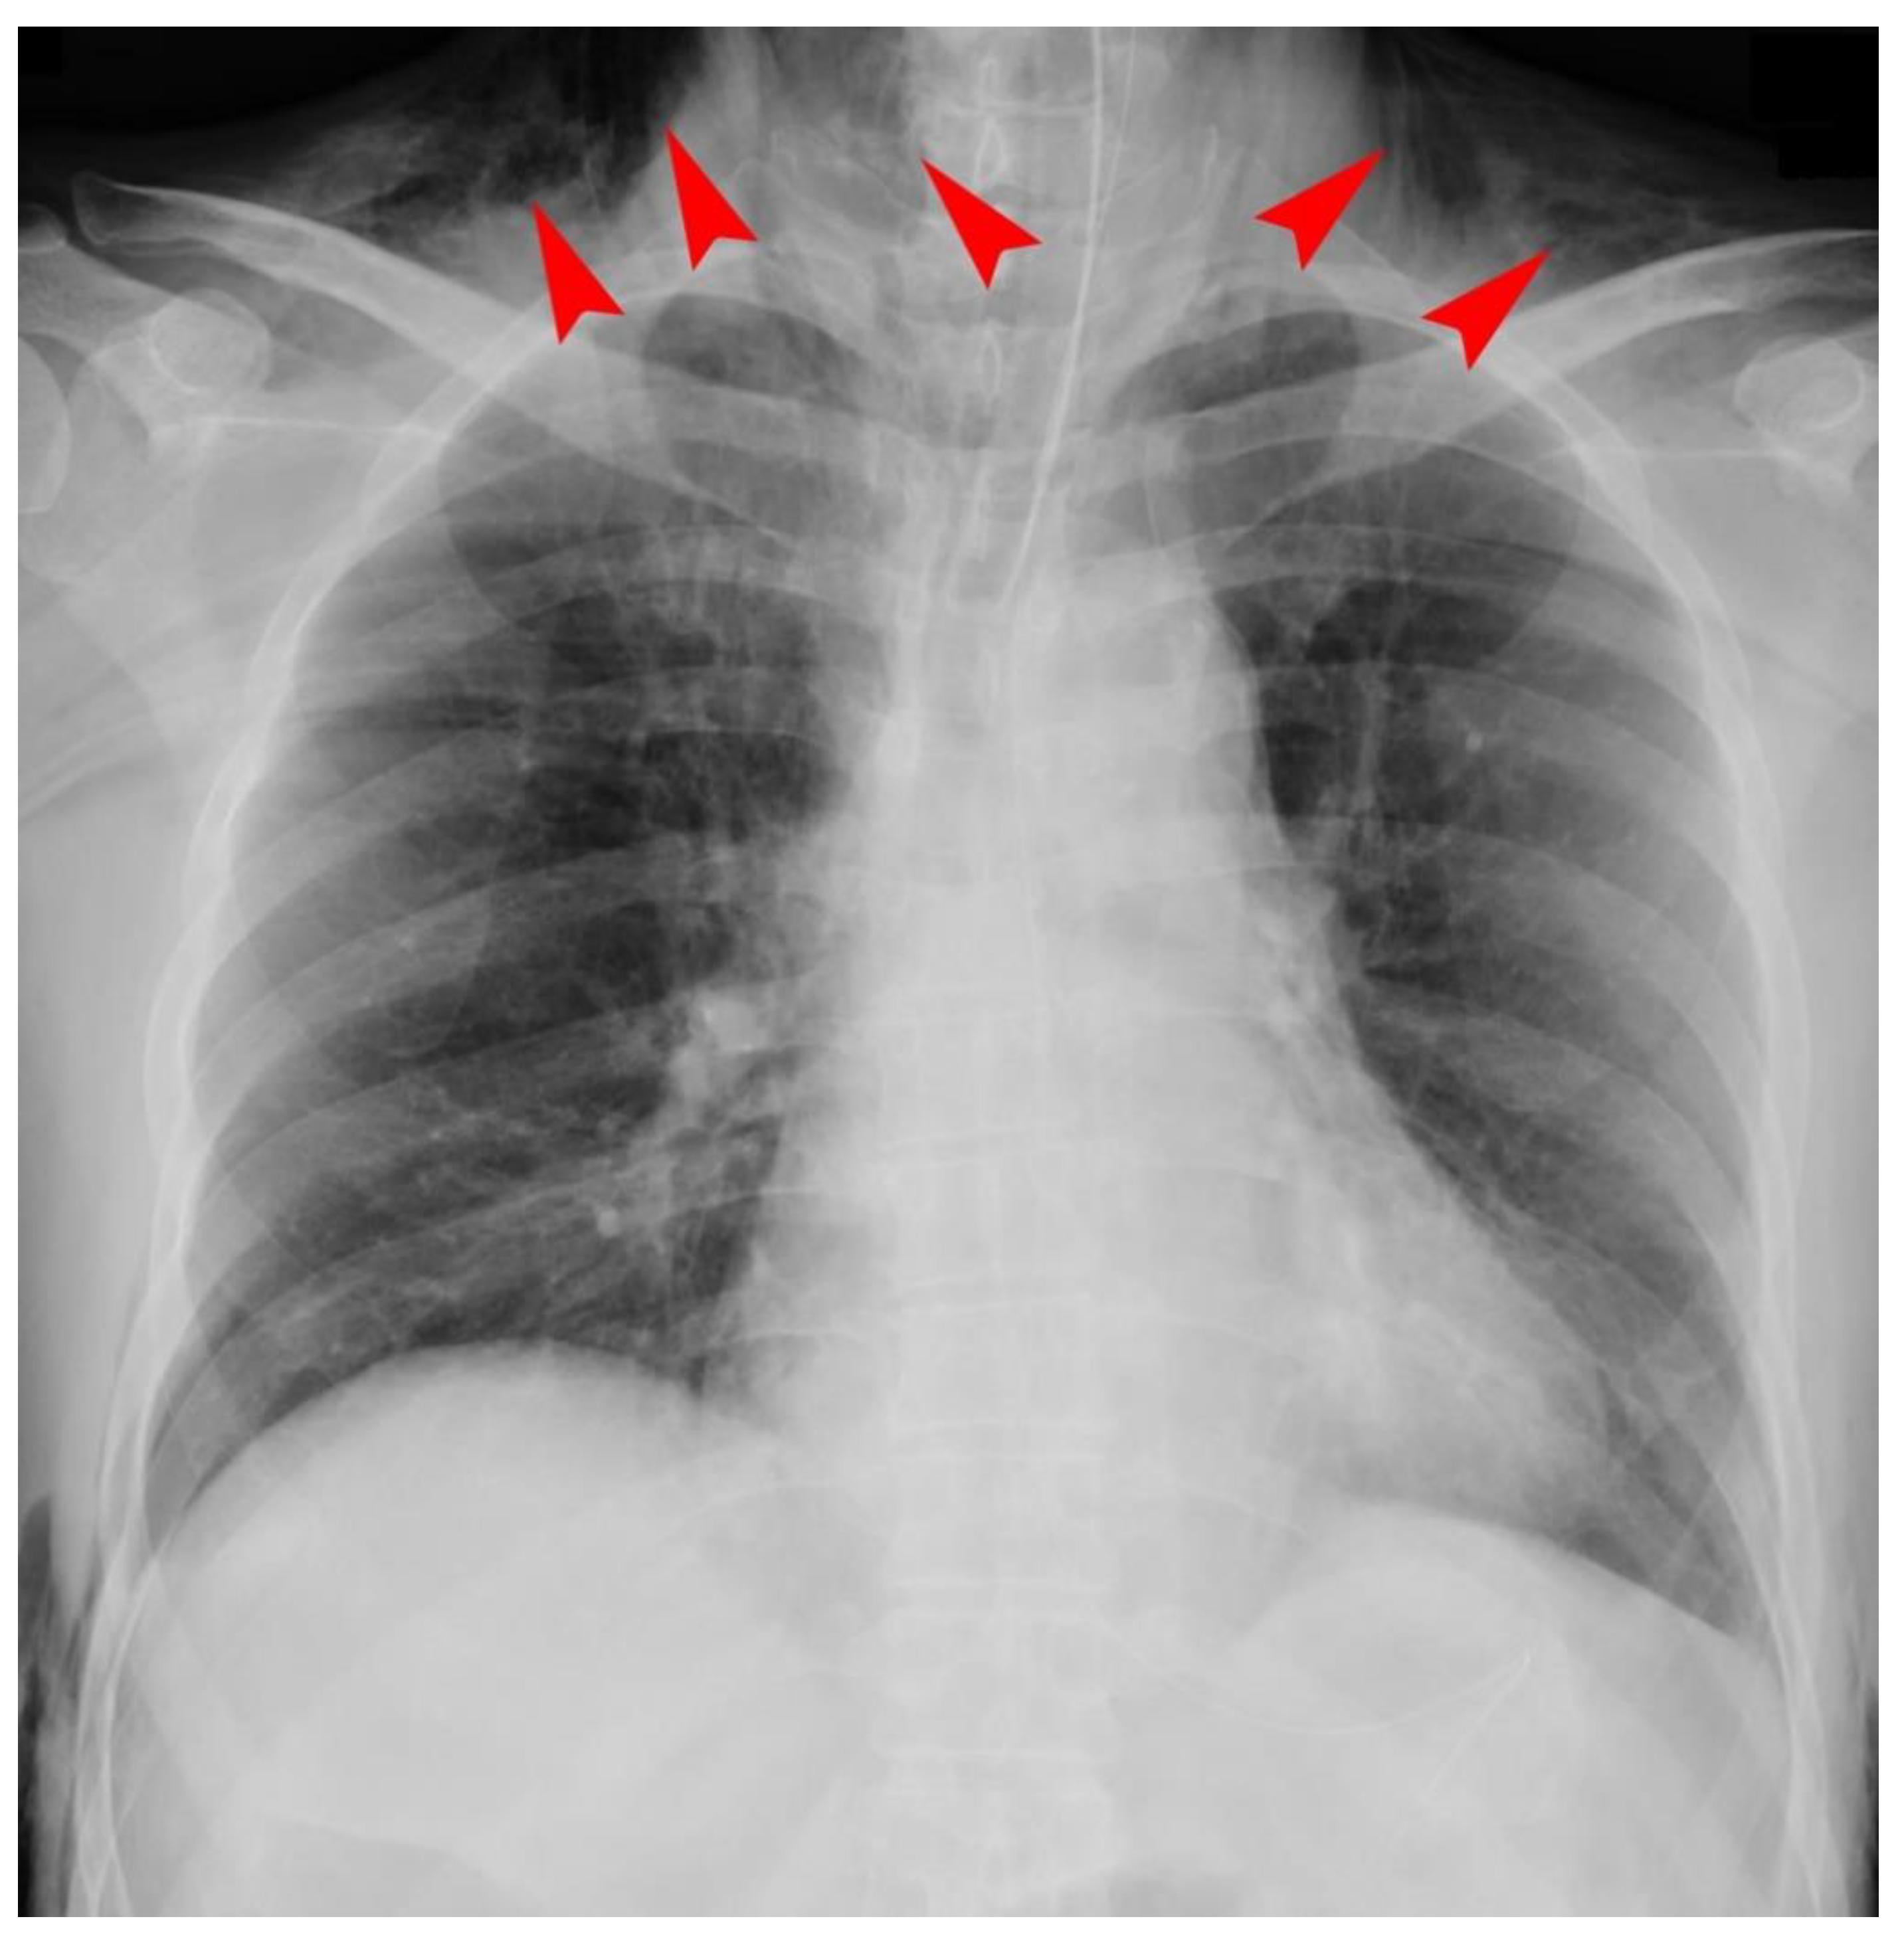

We excluded 29 patients because their chest X-ray findings were inconclusive regarding whether SCE was present or not after the examination of two researchers. We included 229 patients who consecutively underwent RALP in the final analysis. Among them, 209 patients received inhalational anesthesia, and 20 patients received total intravenous anesthesia. We found 55 cases (24.0%) of SCE and no cases of pneumothorax or pneumomediastinum after examining the postoperative chest X-rays. Among the 55 cases of SCE, 12 serious cases had patients with SCE massively extending as far as the neck region (Figure 1). Although the primary clinical sign in such severe cases was sustained hypercarbia exceeding 45 mmHg in PetCO2, we neither recognized any postoperative problems for upper airway patency nor any difficulty in breathing because of the rapid resolution of the hypercarbia after terminating pneumoperitoneum with CO2 insufflation. With the exception of one patient with chronic renal failure who needed to receive hemodialysis in the SCE (−) group, no significant difference was noted in any coexisting disorders such as hypertension, diabetes mellitus, hyperlipidemia, smoking history, and abnormal pulmonary function of the obstructive type between the groups (Table 1). In addition, the development of SCE during RALP did not significantly influence the length of postoperative hospitalization (Table 1). The univariate comparison determined that BMI was significantly less than and the maximum PetCO2 in SCE (+) group was significantly higher than that of the SCE (−) group (Table 1). There was no significant difference in age or operation time the between groups. Multiple logistic regression analysis determined two independent predicting factors for SCE associated with RALP: BMI < 25 kg/m2 (OR: 3.0, 95% CI: 1.25–7.26) and a maximum PetCO2 of 46 mmHg or greater (OR: 23.3, 95% CI: 8.22–66.1) (Table 2).

Figure 1.

A chest X-ray of a serious case of subcutaneous emphysema. Subcutaneous emphysema (SCE) massively extended as far as the neck region in 12 serious cases among 55 SCE (+) cases. Arrowheads indicate SCE in the neck region.